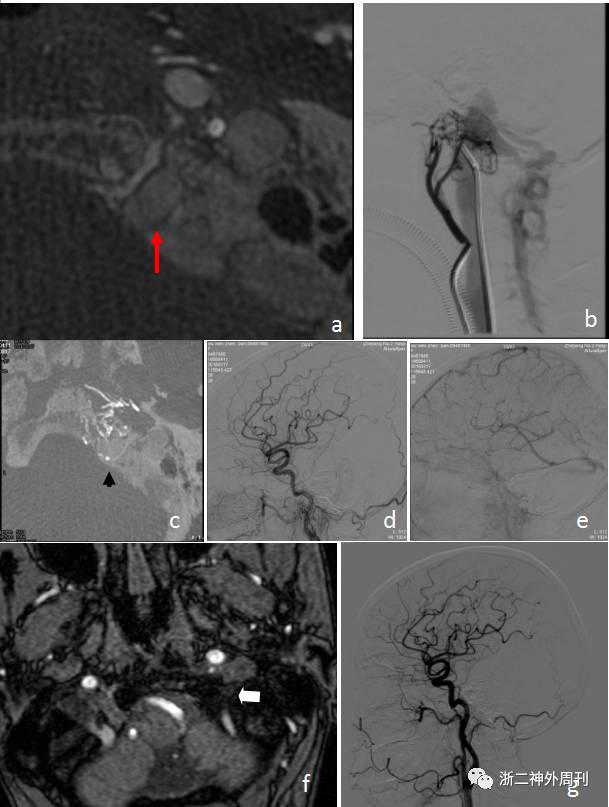

将5F造影管放置到左侧咽升动脉监控治疗效果,然后6F导引导管到位左侧颈内静脉,使用Enchelon微导管(EV3,美国)和Traxcess微导丝(Microvention,美国)尝试超选进入瘘口处静脉球未能成功;遂先使用弹簧圈+Onyx18胶闭塞岩下窦以阻断血流往海绵窦引流,消除眼部症状并改变静脉引流情况;然后成功地将Enchelon微导管(EV3,美国)放置到瘘口处静脉球,超选造影及Xper-CT确认微导管到位,使用弹簧圈填塞静脉球,动脉造影确认瘘口完全闭塞后结束手术。术后3天出院,患者症状完全缓解,无神经功能障碍。术后3个月、1年门诊随访症状无复发,复查脑血管造影未见异常表现(图2)。

图2. a. 栓塞治疗过程中Xper-CT显示左侧舌下神经管处静脉球(红箭头);b. 岩下窦闭塞后左侧咽升动脉造影;c. Xper-CT显示微导管头到位左侧舌下神经管处静脉球(黑箭头);d、e. 栓塞治疗后DSA提示动静脉瘘完全闭塞;f. 栓塞治疗后3D-TOF MRA显示左侧舌下神经管处原有的异常紊乱血管消失,代替为黑色的弹簧圈信号(白箭头);g. 栓塞治疗后3个月数字DSA复查未显示动静脉瘘。